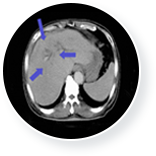

61세 남성 간암 환자는 간 내 다발성 종양 및 복수로 인해 수술이 불가능한 상태였습니다. 또한 간 혈관 변화로 인해 간암 치료 역시 불가능한 상태였습니다.

이때 3개월 간 매주 1회 일정으로 총 12회의 면역세포 치료를 실시하였고, 간암의 종양표 지자인 AFP가 치료 전 19,175(ng/ml)에서 치료 후 170(ng/ml)로 떨어졌습니다.

또한 CT검사 결과 간암의 축소 및 복수 소실이 확인되었습니다.

• 간암 치료 전 이미지

간암 치료 전